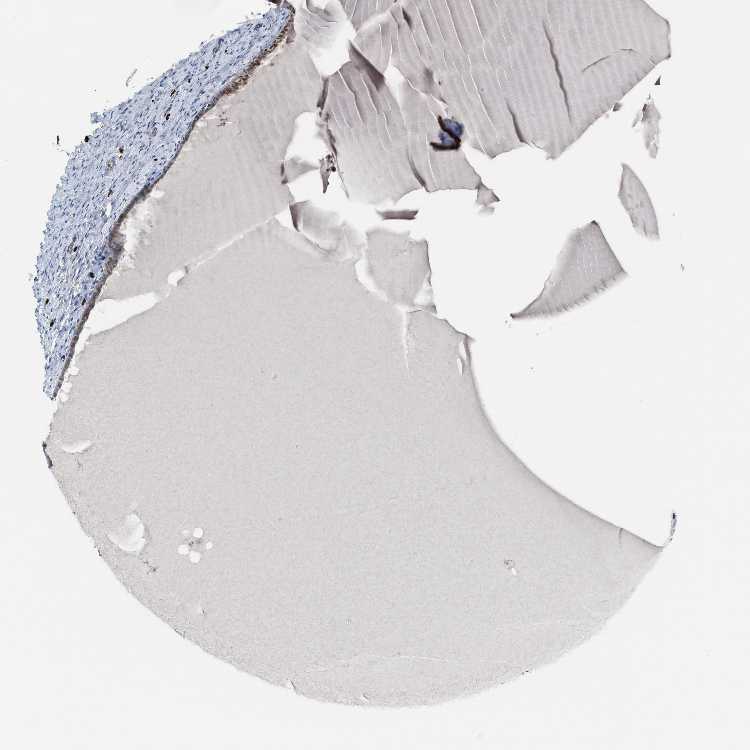

CERVIX - Antibody stainingi

Antibody staining in the annotated cell types in the current human tissue is reported as not detected, low, medium, or high, based on conventional immunohistochemistry profiling in selected tissues. This score is based on the combination of the staining intensity and fraction of stained cells.

Each image is clickable and will lead to virtual microscopy that enables deeper exploration of all samples and also displays staining intensity scores, fraction scores and subcellular localization as well as patient and tissue information for each sample.

Antibody HPA022251

Glandular cells Medium

Squamous epithelial cells Low